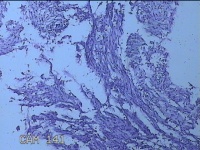

右下肢包块

性别

女

年龄

32岁

临床诊断

皮下结节

一般病史

发现右下肢包块半年余。

标本名称

大体所见

灰白粉红色包块3.8x2.5x1.3cm一个,表面光滑,切开包块呈实性,切面灰白淡黄色,质软。